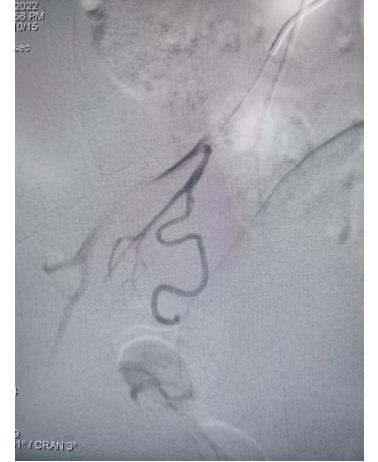

右侧子宫动脉栓塞前后对照